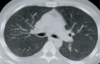

TC ventana pulmonar

Se ven mejor la vía aérea, vasos pulmonares y cisuras, pero todas las estructuras mediastínicas aparecen de un tono gris demasiado similar.

Imagen de TC de alta resolución que muestra fibrosis pulmonar.

Principales utilidades de TC de alta resolución son:

• Valorar el grado de afectación de enfermedades intersticiales pulmonares.

• En pacientes EPOC, para valorar el grado de enfisema y pequeñas zonas de atrapamiento aéreo.

• Determinar la gravedad y extensión de bronquiectasias.

• Valorar qué área es más rentable biopsiar.